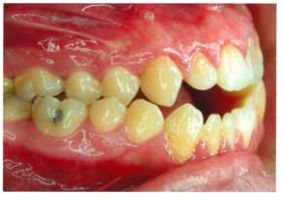

26 下圖是患者矯正後 6 個月的情形,此時最好選用那一種維持器(retainer)以改善此復發情形? (A)活動式維持器(removable retainer) (B)固定式維持器(fixed retainer) (C)主動式維持器(active retainer) (D)功能性矯正裝置(functional appliance)